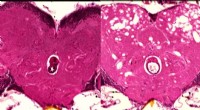

The dugong is a large marine mammal that feeds almost exclusively on seagrass – itself a threatened plant species. At present the dugong is listed as "vulnerable to extinction" on the International Union for the Conservation of Nature red list. Major threats to dugong populations include habitat loss, coastal development, pollution, fishing activities, vessel strikes and unsustainable hunting or poaching.

To monitor dugong populations, researchers typically use aerial surveys or unmanned aerial vehicles. But these techniques are costly, and often affected by difficult conditions such as cloudy water and glare. Additionally, they also provide only a narrow snapshot of what might be occurring in any particular area at a single time.